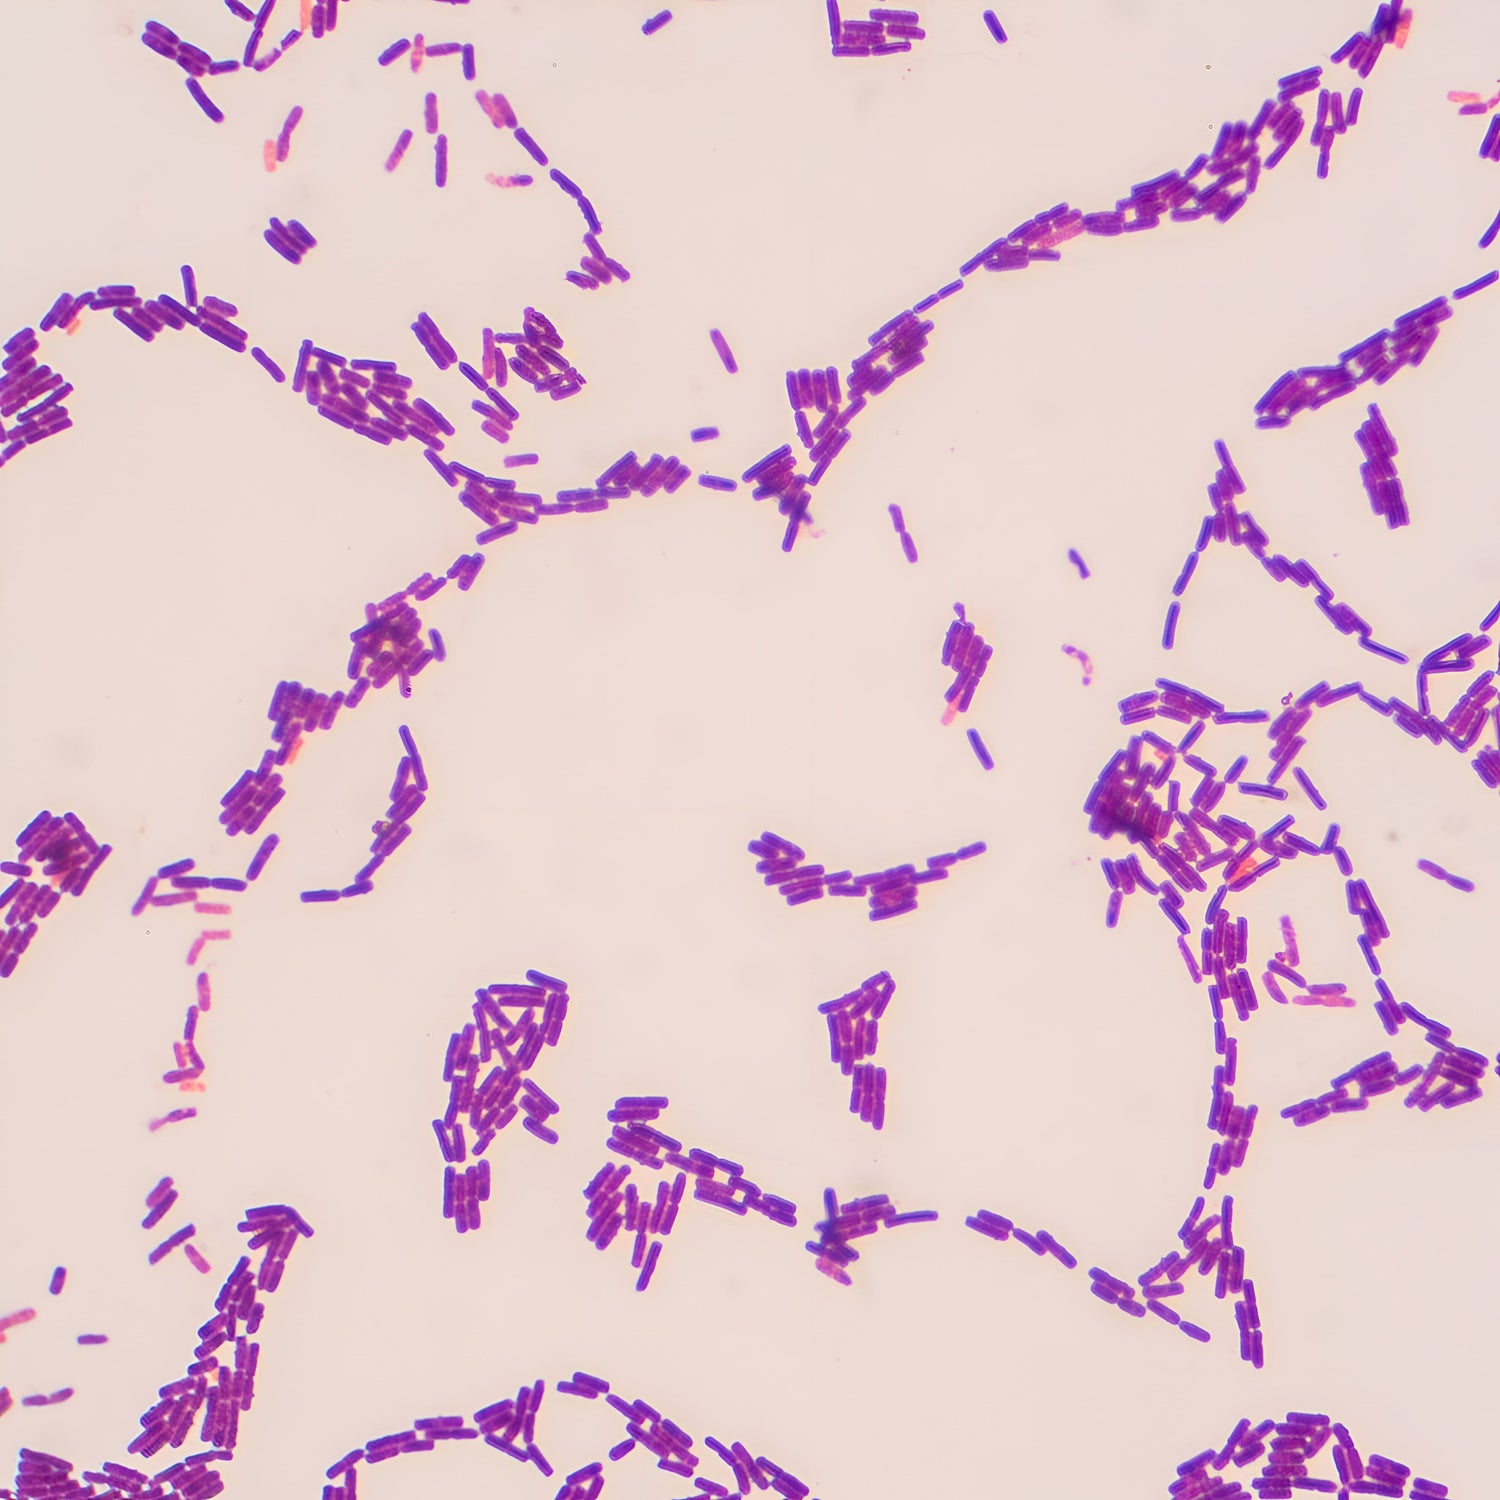

COLLOIDAL SILVER

Learn MoreSilver nanoparticles hold immense promise as therapeutic agents for various medical applications. Their unique properties, including broad-spectrum antimicrobial activity, wound healing potential, and drug delivery capabilities make them attractive candidates for innovative medical interventions.